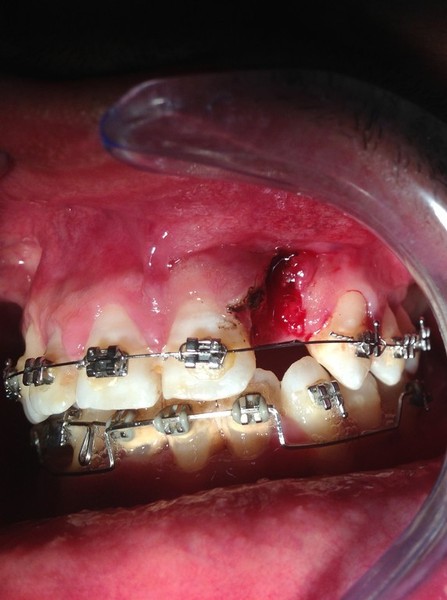

Estrazione radice e inmnesto Epitelio-Connettivale